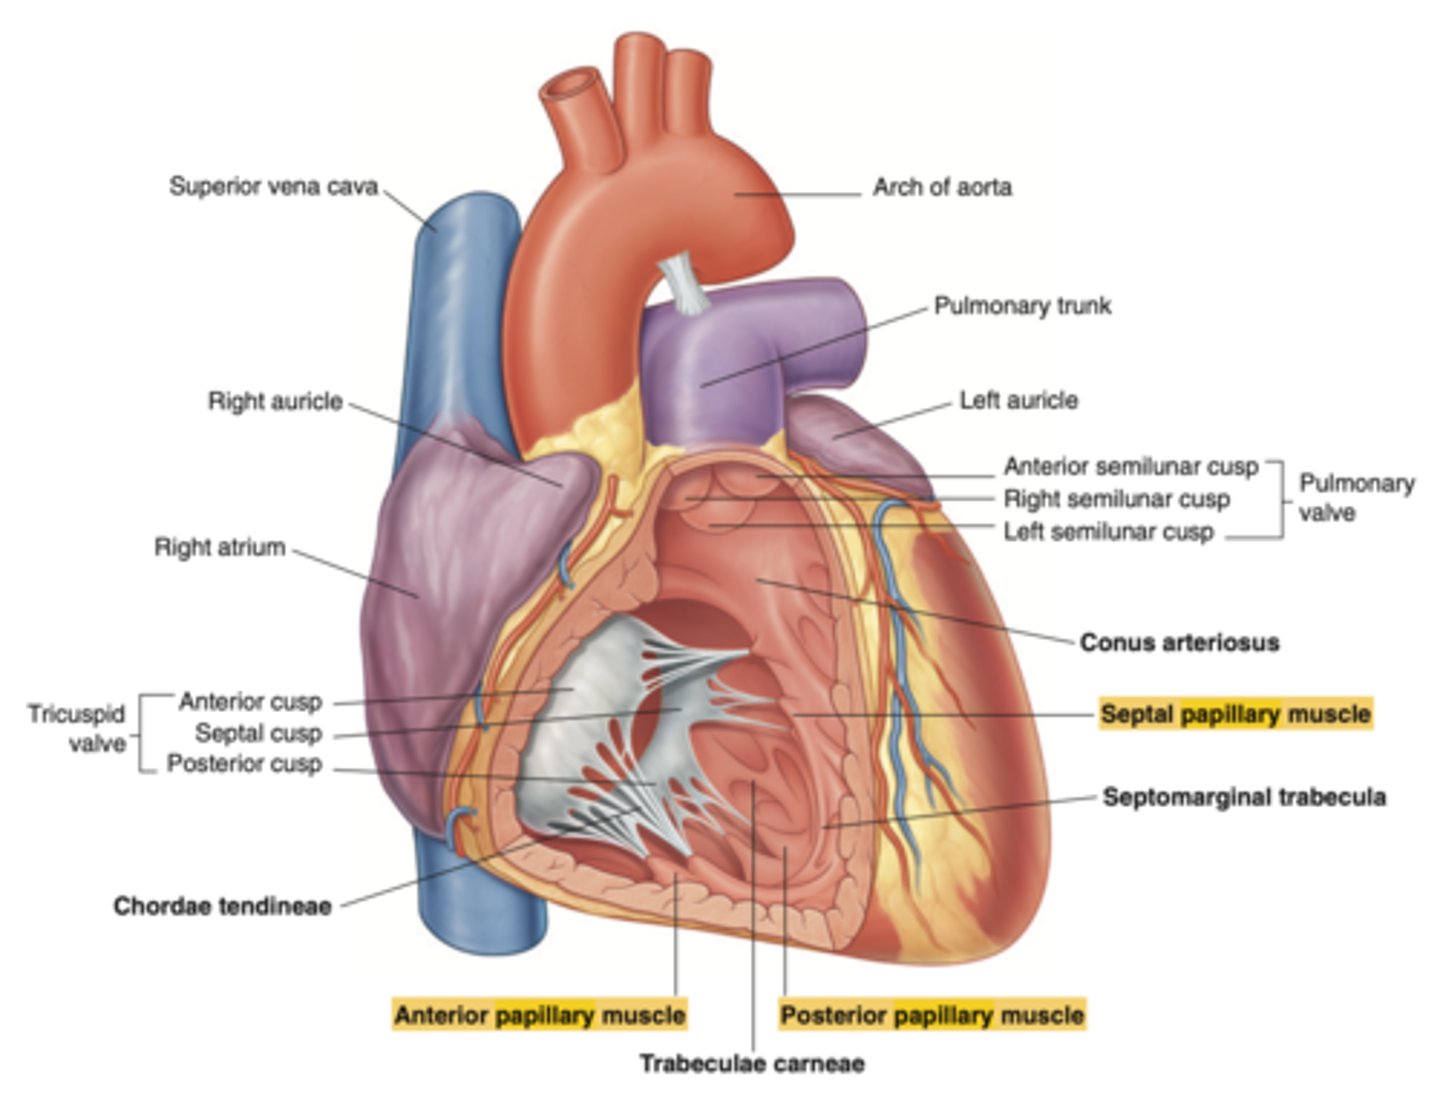

What are the walls of the right ventricle?

. Anterior wall

. Posterior wall

. Septal wall

Right ventricle has a conical shape with 2 o 3 walls

Describe the two portions of the medial/septal face/wall of the right ventricle.

infundibulum or outflow region or conus arteriosus (smooth and membranous)

trabeculae carnae (muscular and irregular)

What are the 3 cusps of the tricuspid valve?

Anterior

Posterior

Septal

What connect the cusps of the valve a to papillary muscles in the

right ventricle?

Chordae tendinae

With the contraction of the walls of the ventricle what's the action of the papillary muscles?

contract as well

With the contraction of papillary muscles what will be happen with the valve?

Close

What is the septomarginal trabeculae (or moderator band)?

Part of the conduction system of the heart.

electrical waves pass through this band to reach the papillary muscles.

LANDMARK

What are the positions of the pulmonary valve cusps?

Anterior

Right

Left